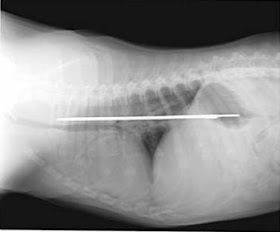

1. Lance Armstrong “screwed”

This is an x-ray image of Tour de-France champion Lance Armstrong’s collarbone. His bones were severely dislocated orthopedic surgeons had to “screw” him with 12-inch long screws. (March 009)